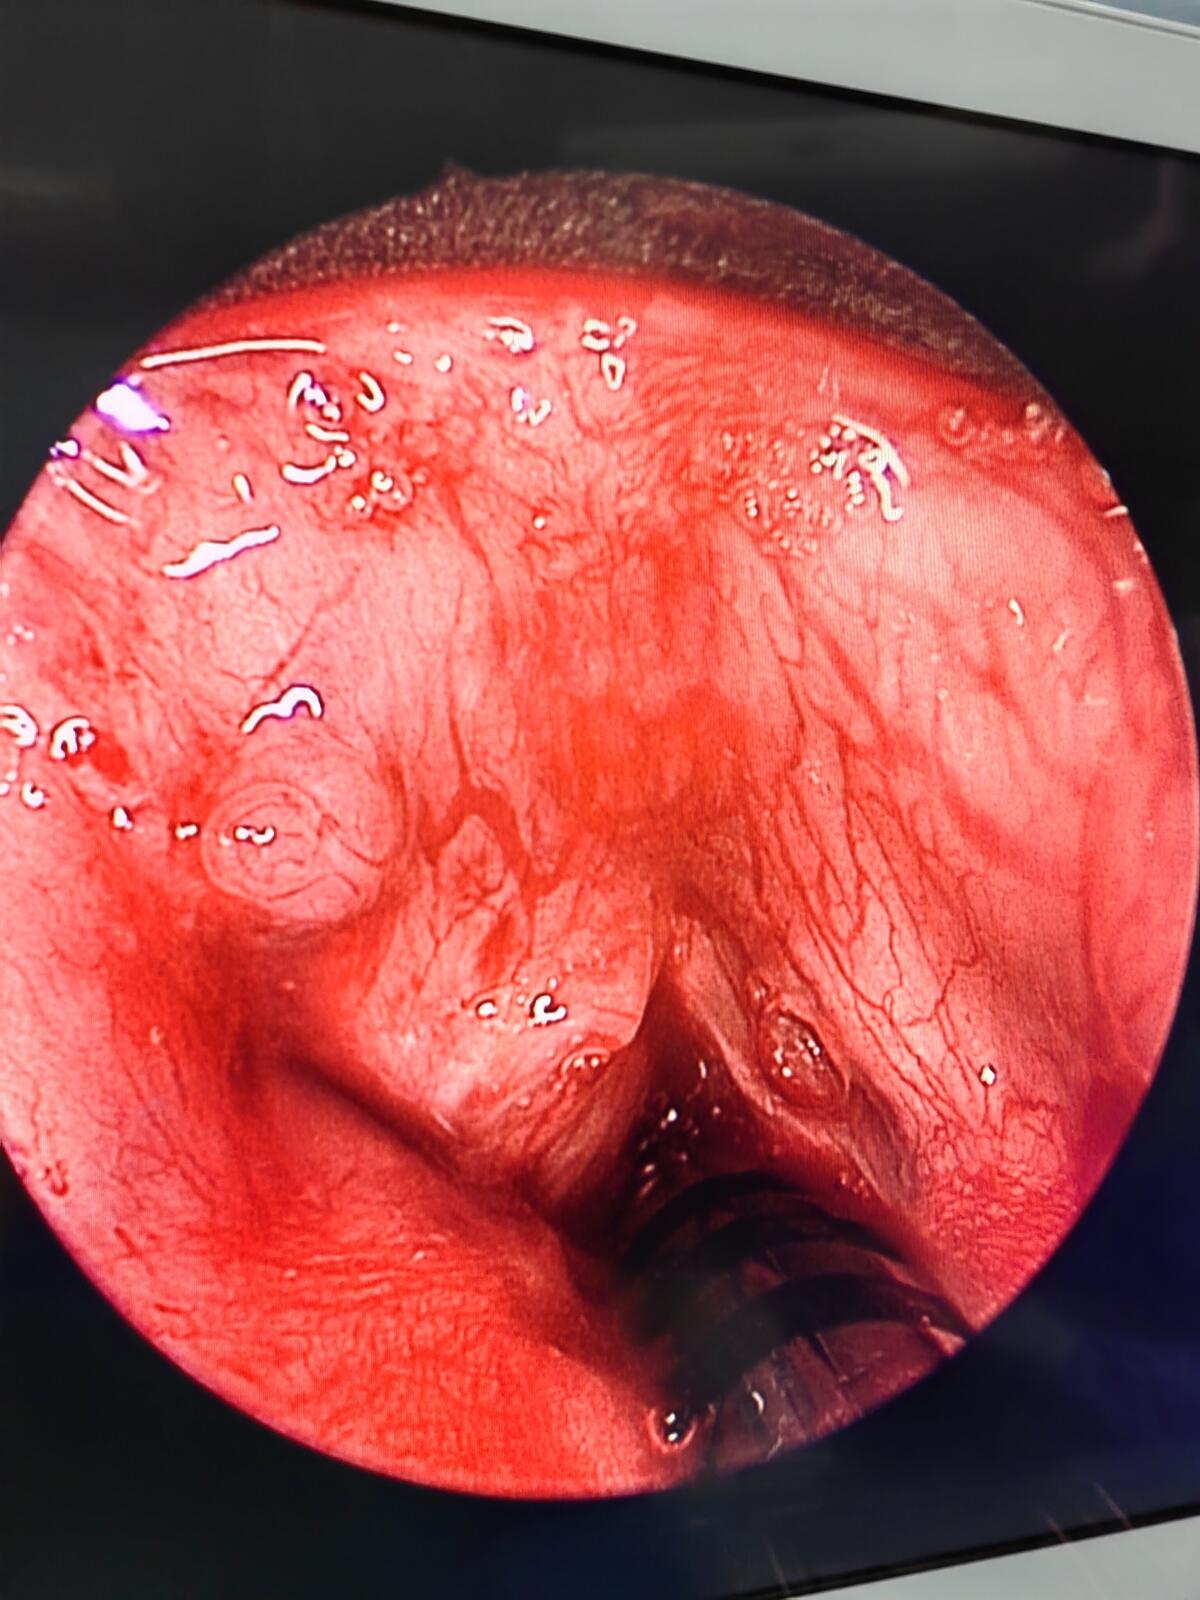

2023年 有幸得到广东省医学会的肯定,我们的内镜下经皮声带外移固定术治疗先天性双侧声带麻痹获得省科技奖。不用气管切开的微创 有效的治疗方式是我们优势。同时我们还有经验丰富的新生儿监护团队。

我们的新技术已覆盖长江以南地区。很多省外患儿家长慕名而来。